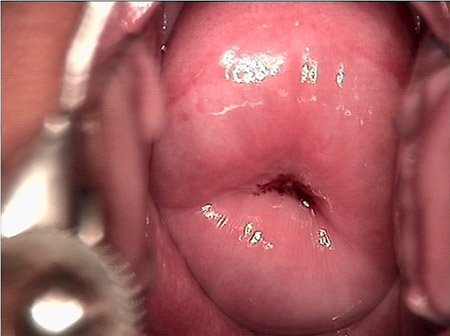

• CIN 2-3 leep術后CIN 2-3 leep術后